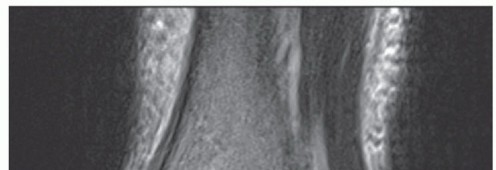

Magnetic resonance (MR) imaging may show an injury to the deltoid ligament (FIG 4), particularly in acute conditions, and it may also reveal pathologic conditions of the posterior tibial tendon.

FIG 4 • Proximal avulsion of the deltoid ligament. AP MR imaging reveals a complete avulsion of the deltoid ligament to the medial malleolus.*